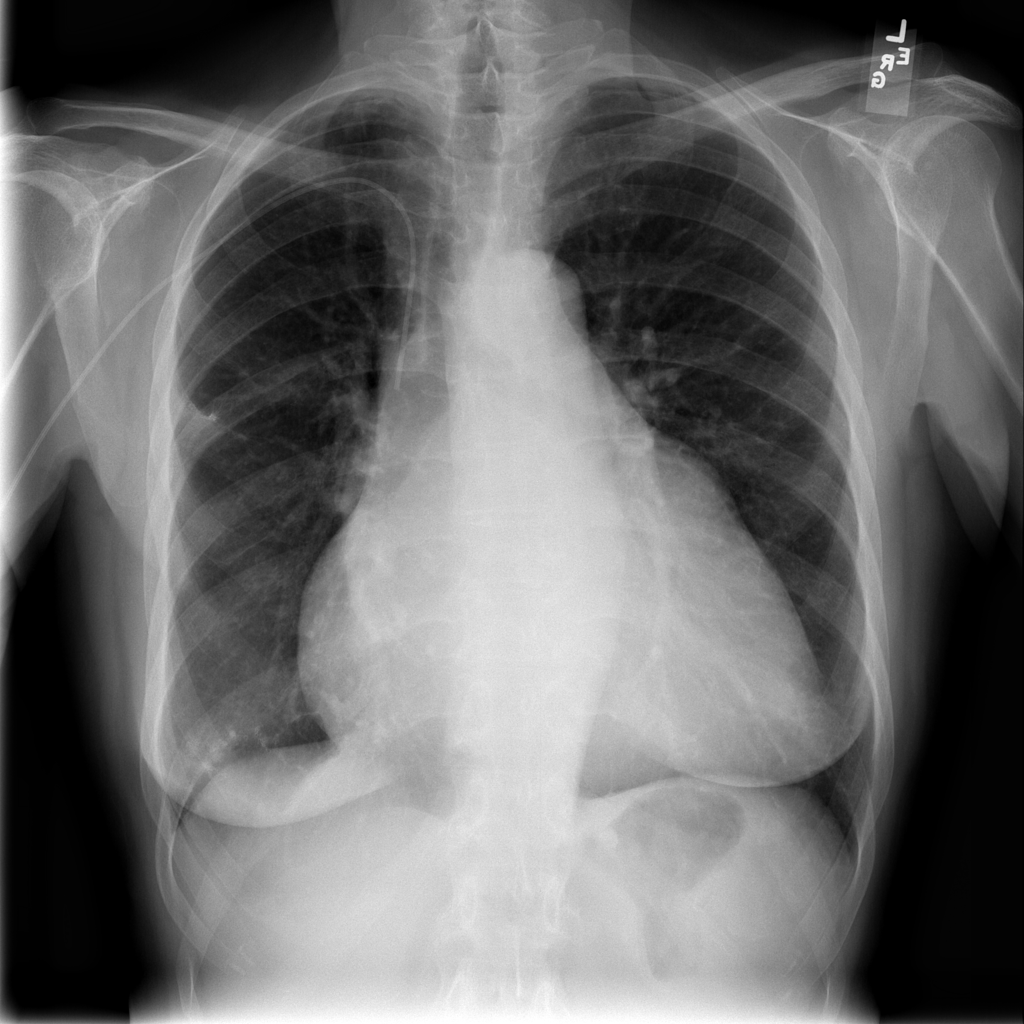

PAT-E81B · IMG-000Effusion

PAT-E81B · IMG-000

PA